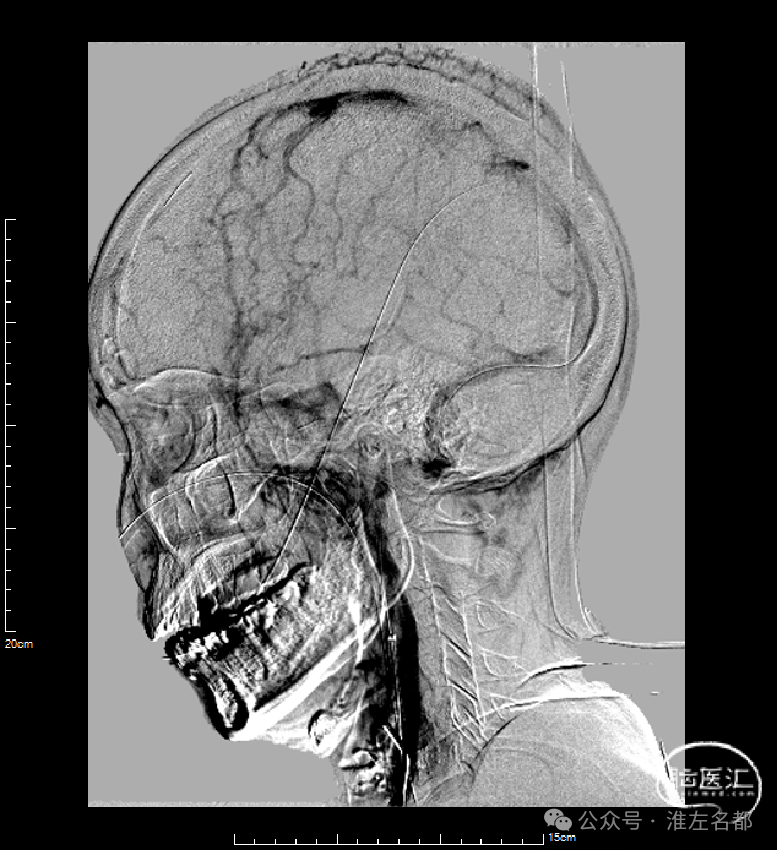

右侧颈动脉造影(正侧位):上矢状窦和直窦未见显影;右侧横窦和乙状窦少许显影。

左侧颈动脉造影(正侧位):上矢状窦前部少许显影,直窦未见显影,左侧横窦和乙状窦显影纤细。

右侧股动脉穿刺置5F鞘,股动脉造影路图下穿刺右侧股静脉,置入8F鞘。6F长鞘(90cm,Cook)+6F中间管(115cm)+4F多功能管(125cm)组成同轴,泥鳅导丝导引下进入右侧颈内静脉颅底位置。泥鳅导丝超选进入右侧乙状窦和横窦,4F多功能管跟进乙状窦一段距离后难以继续前进,此时6F中间管在内衬4F管支撑下进入乙状窦,并前推进入横窦,成功建立治疗通道。

微导丝(Command 14)微导管配合,进入上矢状窦中部,交换出微导管,保留微导丝作为参照,引导后续微导丝微导管超选直窦。

微导管微导丝(Command 14)超选直窦成功后,交换出微导管。经微导丝送入3*30mm球囊,扩张直窦近段,并以BAT技术将6F中间管推送入直窦内,行血栓抽吸操作,吸出多量红色血栓。

介入治疗后右侧颈动脉造影:上矢状窦、直窦和右侧横窦-乙状窦均见显影,右侧横窦局部狭窄明显。